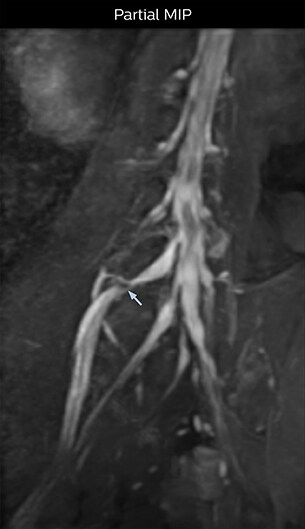

At Northern Fukushima Medical Center in Japan, excellent MRI visualization of nerves helps support confident diagnoses and informs surgical treatment decisions for patients with lower limb symptoms. MRI technologist Tanji and orthopedic surgeon Dr. Yabuki share how direct nerve visualization with the 3D NerveVIEW method adds information when diagnosing atypical herniations. The additional insights changed their way of working and benefit their patient care, as illustrated by some clinical examples.

“In patients with lower extremity neurological symptoms, NerveVIEW helps us to determine the disease matching the patient’s symptoms by directly visualizing the nerves. We use the sequence mainly, when there is suspicion of intraforaminal stenosis, extraforaminal stenosis or lateral disc herniation, which is often based on routine T2- and T1-weighted images. Additionally, the excellent depiction of the course of nerves makes NerveVIEW a good navigator when applying treatment such as block therapy or surgery.”

“In such case, we would then browse through axial T2-weighted MR images slice by slice and mentally reconstruct the actual situation based on both radiculography and MRI. Fortunately, NerveVIEW can now very well show nerve courses and presence of nerve compression or edema in one single image series.” “We have often seen NerveVIEW directly depict details of the nerve compression that were not observed by radiculography. Therefore, we think that with NerveVIEW we can reduce the number of invasive examinations, especially for some patients with lumbar plexus symptoms.”

“Before NerveVIEW, diagnosis by MRI alone was sometimes difficult, unless there was a strong suspicion based on clinical symptoms,” says Shoji Yabuki, MD, DMSc, Orthopedic surgeon at Fukushima Medical University School of Medicine. “This is why we routinely perform selective lumbosacral radiculography (nerve root block) and x-ray in such cases. However, radiculography can only depict nerves as far as the contrast agent reaches. When a nerve is distorted by compression, the contrast agent will not pass through this compressed area, preventing us from evaluating the full nerve compression.”

The key concept in MR neurography, Dr. Yabuki stresses, is the ability to directly visualize spinal nerves, versus inferring the presence of pathology indirectly. “Before NerveVIEW, we estimated compression of the nerve by looking for the presence or absence of fat signal on other MR images,” he says.

“For example, in sagittal images, when the presence of fat is observed in the intervertebral foramen, it suggests that there is a margin around the nerve. Similarly, the absence of fat indicates that the nerve is being compressed. So, we used to deduce nerve compression indirectly. With NerveVIEW, however, we can observe the condition of the nerves directly, regardless of the presence or absence of fat. We always prefer such direct observation of anatomy over having to make an inference about it.”

“Although symptoms of typical disc herniation and atypical hernia are very similar, the actual site of herniation is different. It is therefore important to characterize the nerve’s condition both inside and outside of the intervertebral foramina. “Conversely, if we see no abnormality in NerveVIEW, we can assume at least that there is no severe condition that requires surgery. Like this, it can help us avoid unnecessary surgery. NerveVIEW can have a tremendous impact in this way.”

“NerveVIEW is really useful for those cases where a nerve disorder is strongly suspected based on the clinical examination but our regular MRI images do not show any findings. These atypical herniations and spinal canal stenosis, occurring in 5% to 15% of the total lumbar herniation/stenosis cases are our main target when using NerveVIEW,” says Dr. Yabuki.